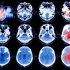

10 Concussion Signs for Coaches to Watch For.

As sports seasons are getting into full swing, coaches must be watching their athletes to be sure that none have suffered from a concussion without knowing it. In contact sports, it is very common for a student to sustain a concussion without even knowing it. Here are some things to watch for to make sure that if your players have sustained one, they are treated immediately!